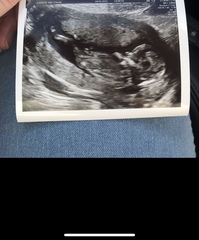

As an example these are my ultrasound direct scan pics from 12+6

Private Scan- Clinic Recommendations

Moominmiss · 06/07/2021 09:35

And these are my window to the womb ones from 2 days earlier at 12+4

AllSinging · 06/07/2021 09:41

AllSinging · 06/07/2021 09:42

@Moominmiss oh wow, that is a difference! Thank you for sharing, I really appreciate it!